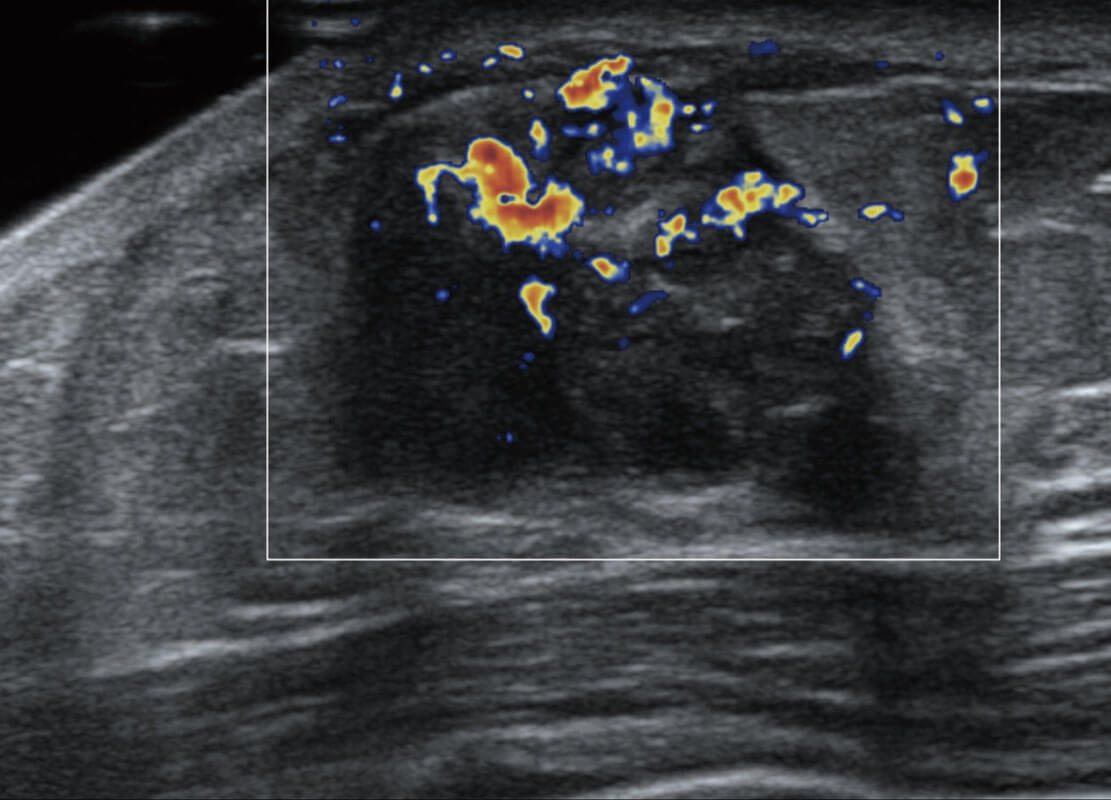

乳腺超声 / 新生儿

P60搭载宽频带线阵探头、宽景成像、弹性成像技术,为您提供乳腺应用方案。P60支持高频相控阵探头、线阵探头、腹部高频探头、腹部微凸探头等,丰富的探头群搭载敏感的彩色血流成像,适用于新生儿多种脏器检测要求,满足新生儿筛查需求。

• 乳腺导管癌

• 乳腺癌显微血流

• 新生儿肝血管癌

• 新生儿脊髓圆锥

• 新生儿心脏